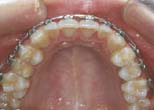

Ant. space closure or redistribution without movement of post. teeth